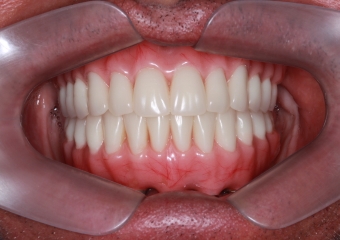

Imagem Inicial,em 2015

Sorriso inicial, em 2015